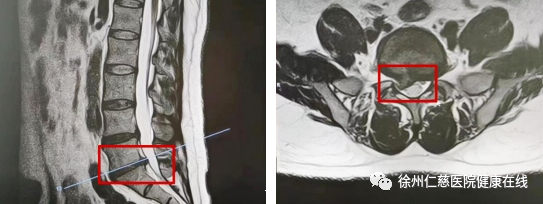

手术前后对比

煎熬了1个月也不见腰痛好转,8月上旬,李师傅在家人的搀扶下来到betway在线登陆脊柱外科门诊,betway在线登陆脊柱外科副主任医师张冶接诊后,结合影像资料并仔细查体后,诊断李师傅为腰椎间盘突出伴腰椎椎管狭窄,有明显的手术指征。

经过充分的术前评估和准备,脊柱外科副主任医师尚军、张冶以及主治医师郭松组成的手术团队在麻醉团队和护理团队的密切配合下,为李师傅顺利摘除了腰椎间盘突出的髓核,并解除腰椎椎管狭窄,术中出血约5ml。术后当天,李师傅疼痛症状随即得到缓解,第二天,即可下床活动。